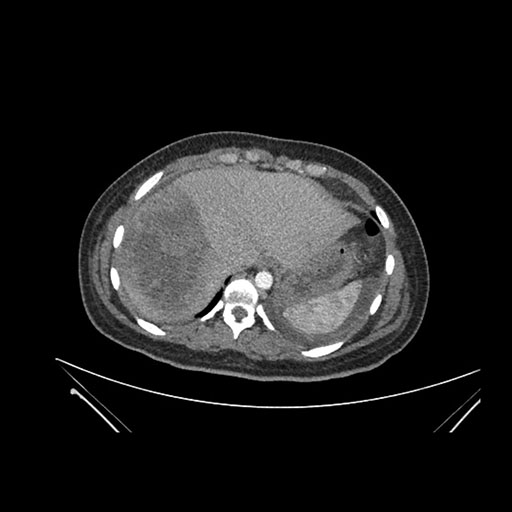

Imaging Analysis

Look through the patient's CT scan to identify any areas of concern for the necessary procedure.

Axial Arterial

Based on initial findings, which issue(s) would you be most concerned about?